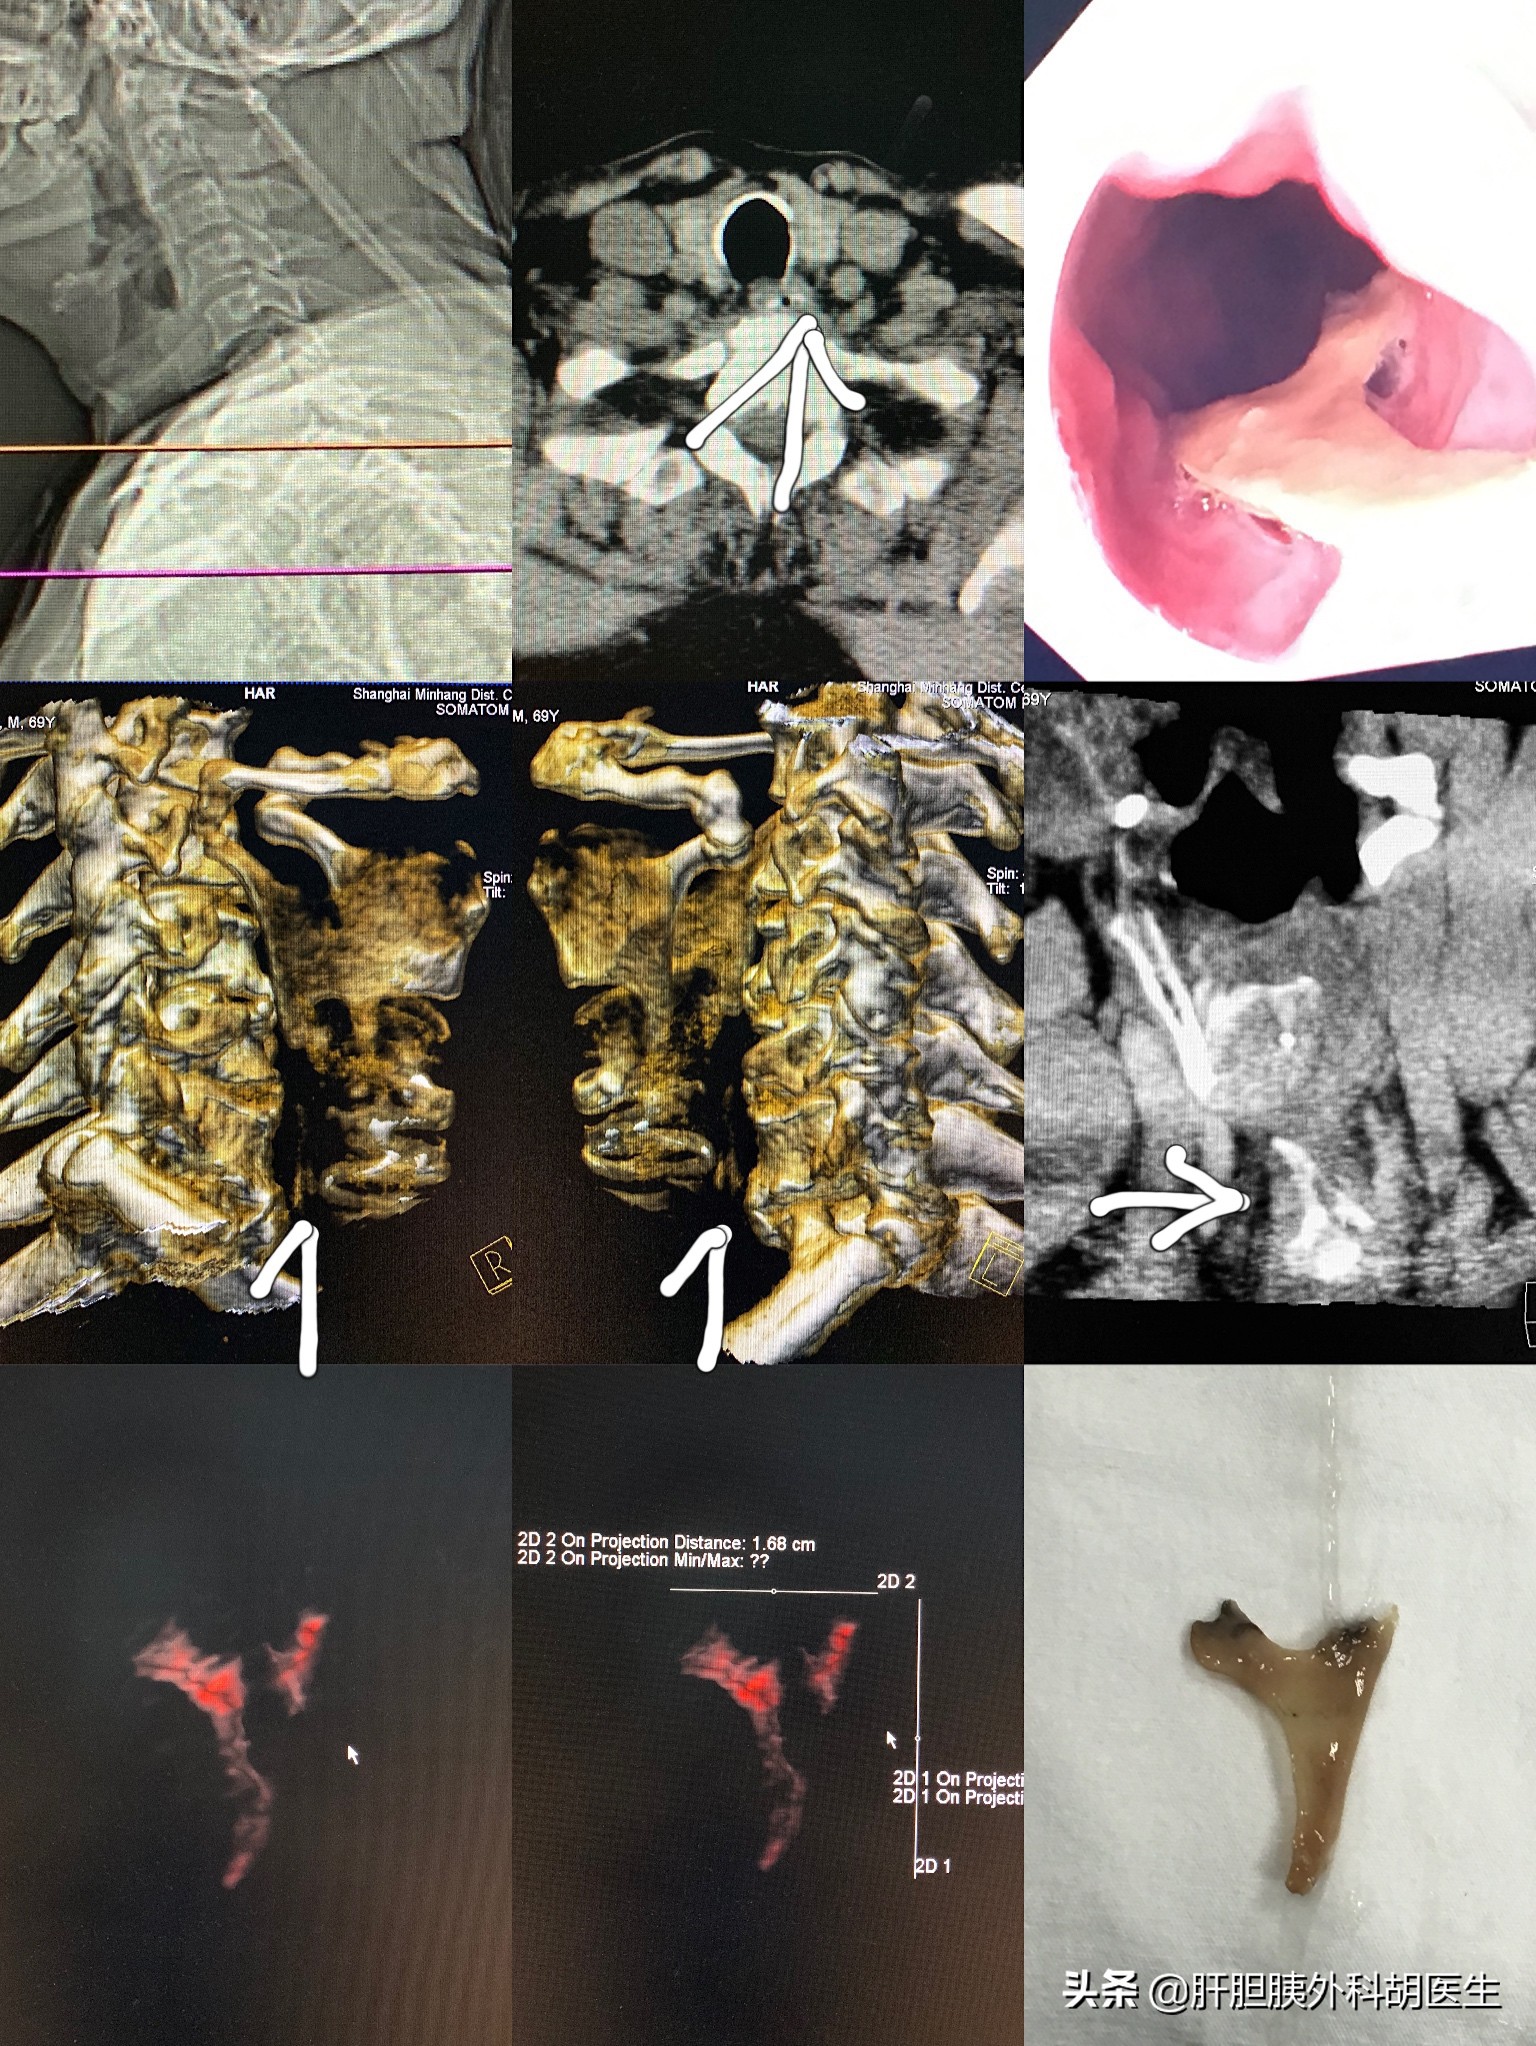

驱车赶到我们医院,再次叫五官科医生检查,还是没有看到鱼刺。这边还没有喉镜,这时候就有点焦虑了,目前这种情况,并不清楚鱼刺的位置,或者鱼刺已经进入胃部,咽喉部仅仅是刚才扎伤后引起的不适。现在到底是直接到其他医院再做喉镜检查呢,还是直接做急诊胃镜检查呢?这时就体现了在自己医院的便捷性,咨询后去做了颈部CT检查,通过重建发现咽喉部确实有高密度的鱼刺存在,而且体积较大,位置已经到了食管入口处。评估下来喉镜取也较为困难,一不做二不休就把胃镜医生从家里叫过来,通过胃镜顺利取出了“元凶”。

以前鱼刺卡喉,通常叫五官科医生镜子一照,用镊子直接就可以取出;再不济,做了喉镜,必定能取出来。这次,由于之前老爷子在卡了鱼刺后,吞了口饭的缘故,骨头位置较深,使用喉镜也未能取出,最后动用了胃镜才将其取出。虽说绕了些弯路,但最终结果还是完美的。之前听说有人喉咙卡了鱼刺,做了无痛胃镜才将其取出,而鱼刺已刺穿食管,距离后方的主动脉很近了,炎症反应明显,只能禁食不吃东西,前后挂了2周的盐水才好透。也有人鱼刺进入胃、小肠,刺穿肠管,引起腹膜炎,做了开腹手术才好。正所谓,鱼刺虽小,也能致命!